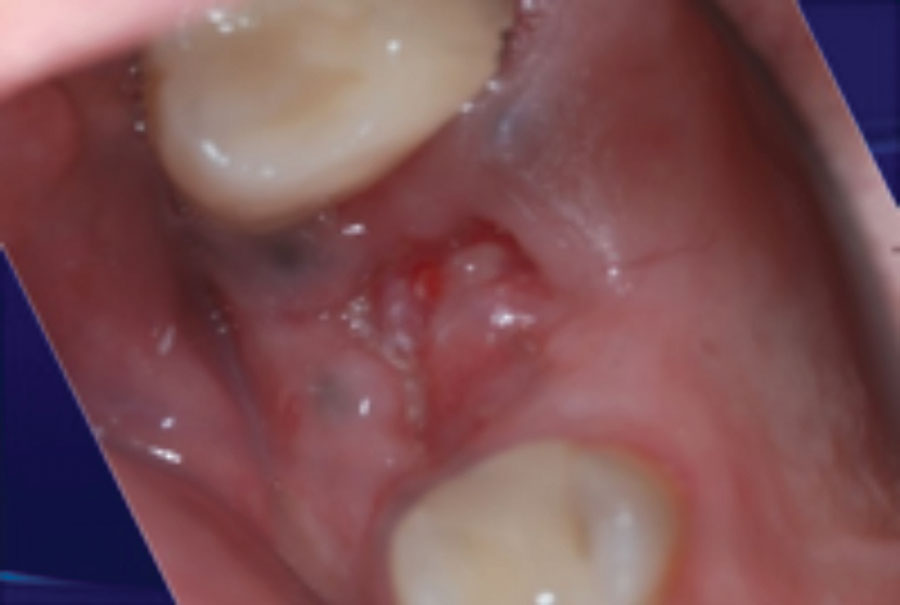

Keys to Predictable Socket Grafting – Part 1

To satisfy the ideal goals of implant dentistry in a predictable manner, hard and soft tissues should present in ideal volumes and quality. The alveolar process is affected so often after tooth loss that socket grafting is usually indicated to achieve optimal results. Reasons for socket grafting include an improved esthetic appearance particularly in the anterior alveolar ridge, preservation of remaining … Read more